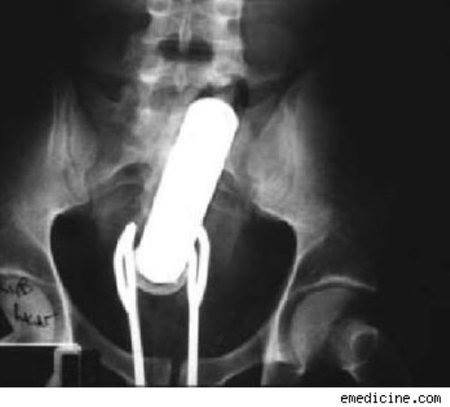

Lâmpada:

Esse foi difícil de engolir e de retirar, e pra piorar a lâmpada é muito resistente, deu uma trabalheira.